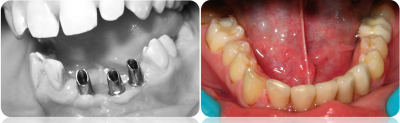

Gallery

Galeria